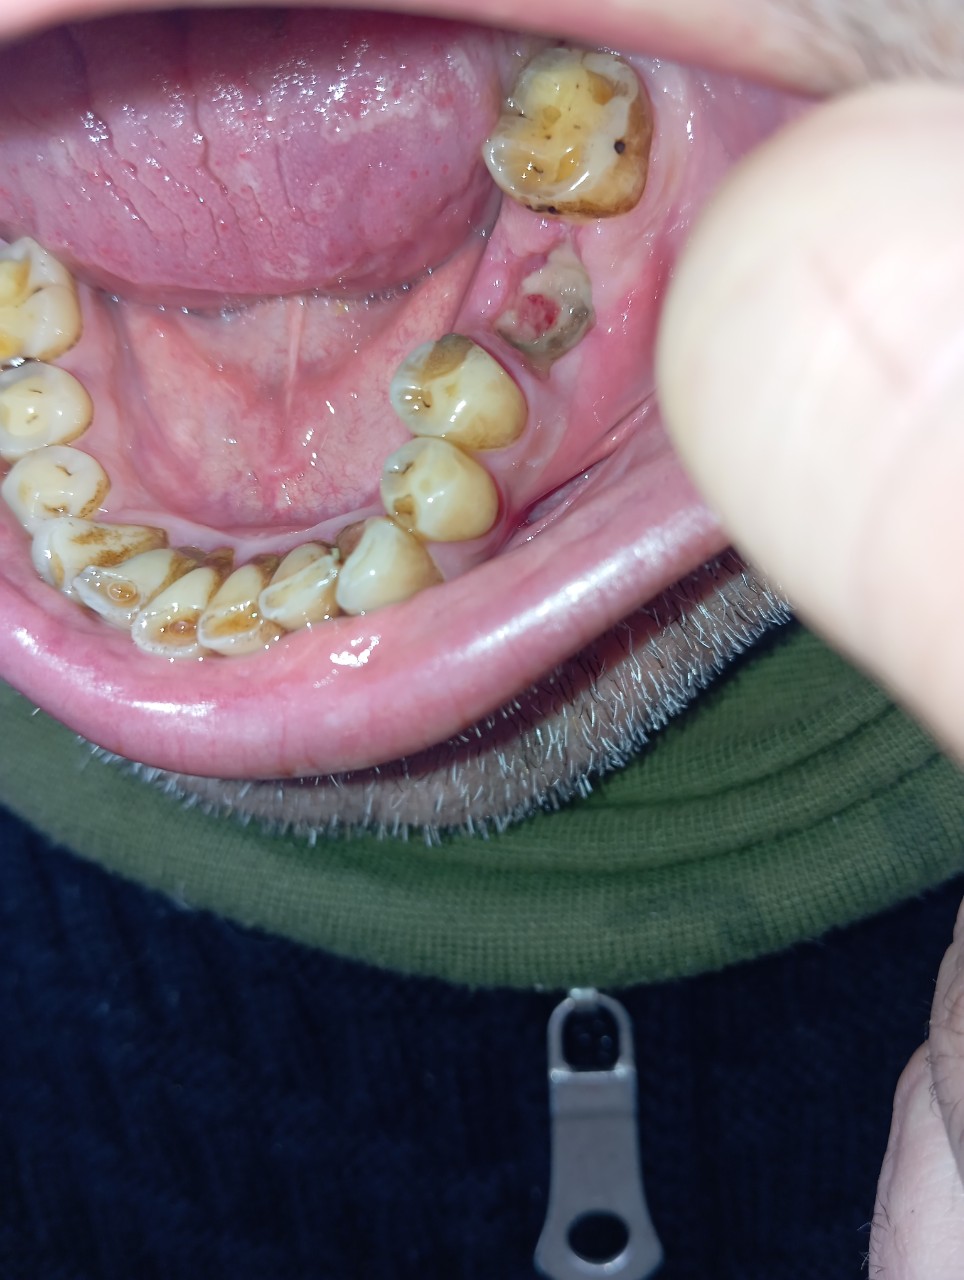

Вітаю, Добрый день. Неделю назад у меня начала болеть десна в нижнем ряду за седьмым зубом. Там как бы ранка Толи трещина и подпухло немного. Та восьмерка седит крепко. Мне 46 доктор говорил шо она уже не выйдет. Так вот через пару дней добавилась боль в шестом или седьмом зубе. Пульсирующая боль. Ночью не спал почти. Утром сегодня поехал к хирургу он удалил шестой зуб так как он плохой на снимке. Теперь я думаю решил ли я проблему, или это будет продолжаться и в е это из-за восьмёрки? Как думаете на снимке есть восполнение которое давало боль? Спасибо

"Теперь я думаю решил ли я проблему, или это будет продолжаться и в е это из-за восьмёрки? Как думаете на снимке есть восполнение которое давало боль? " - Есть воспаление, зуб удалили правильно. Но боль, которую вы испытывали, скорее всего, была связана с воспалением десны над восьмым зубом, так как всё от туда начиналось.

Я ещё не пойму что болит. Было сложное удаление. Там на снимке киста была на шестерка? А семёрка на снимке нормально?

"Там на снимке киста была на шестерка? " - Не киста, но гранулема, т. е. очаг хронического воспаления вокруг верхушки корня.

"А семёрка на снимке нормально? " - Да, нормально.

Добрый день. Позавчера был в челестно лицевой областной с сильной болью. Альвиолит. Почистили все. Выписали антибиотик моксиклав и доксициклин. Болит ужасно сильно соседний зуб пятый. Как при пульпите. На нем есть темное пятнышко но свиду зуб нормальный. Я не знаю шо делать уже с ним. Хирург сказал что зуб хороший. Но он же сильно выражено болит. Даже лунка не так болит. Как Вы видите на снимке он норм?

"Десна побелела вся. Эт норм)? " - Это последствия удаления зуба. Это ишемия и некроз слизистой. Ничего страшного. В течении 7 дней она станет красной и где-то через месяц вся лунка затянется новой тканью.

"вот на зубе пятом черная точка может это все же он больной? " - Да, там, скорее всего, имеется кариес под пломбой, но причина ваших болей в данный момент — альвеолит, как осложнения после удаления зуба. А пломбу в 5-ом зубе можно будет заменить после заживления лунки удаленного зуба, т. е. где-то через месяц.